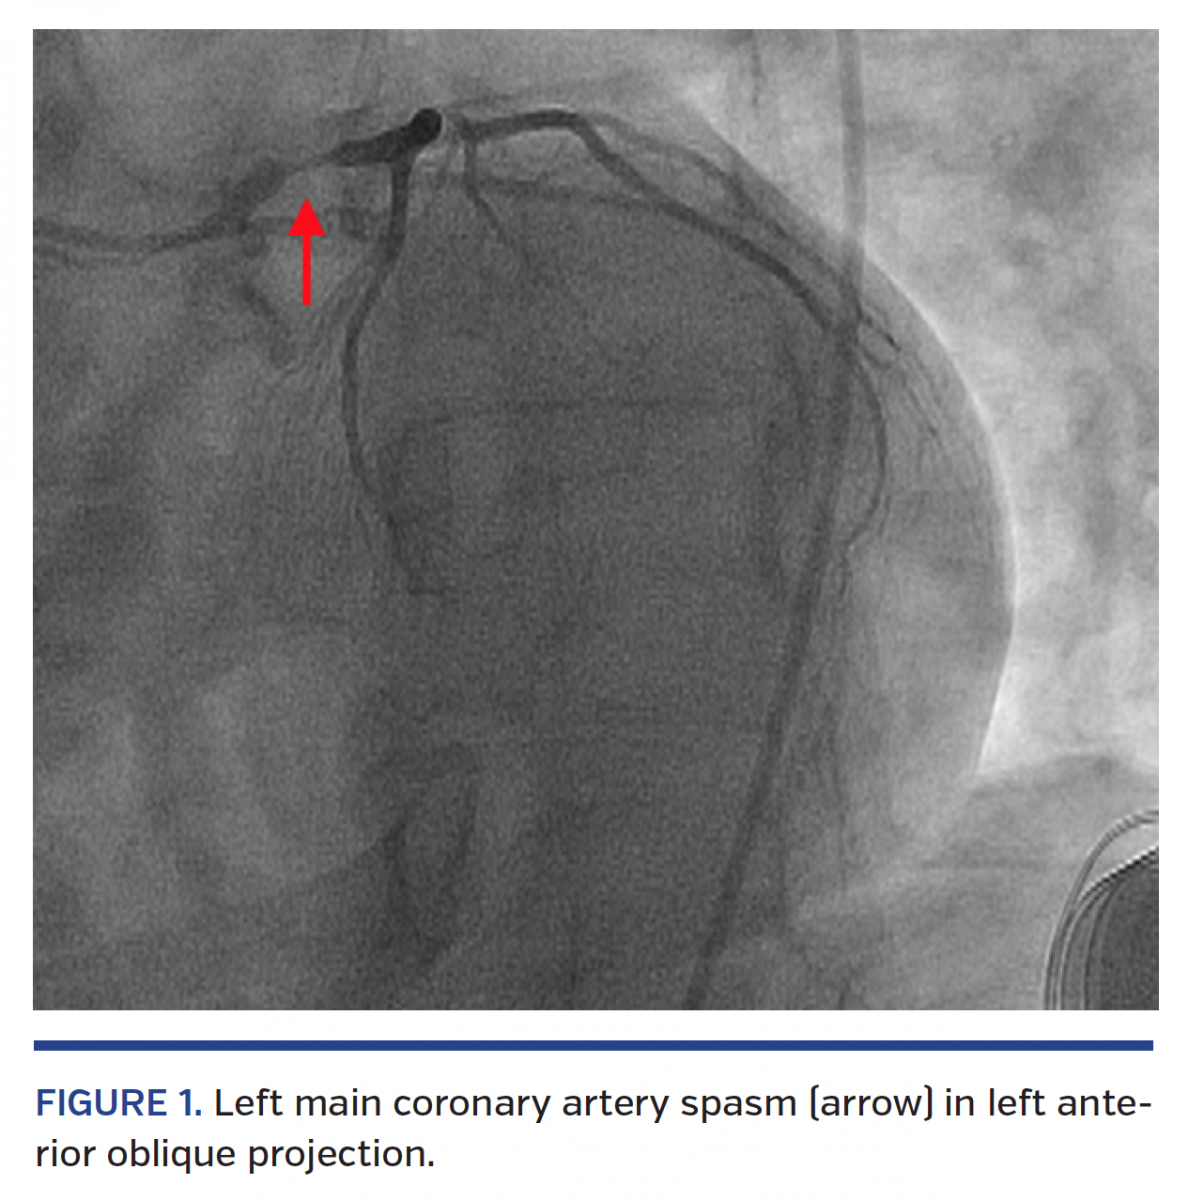

Persistent Catheterinduced Coronary Artery Spasm ppt download

Persistent Catheterinduced Coronary Artery Spasm ppt download Spasm With Catheter And, people with a neurological disorder, such as ms or a spinal cord injury, may experience. Bladder spasms may occur because the catheter is unstable inside the bladder, as a result of a neurogenic bladder, an irritable. Medical conditions such as neurogenic bladder, multiple sclerosis,. Bladder spasms can also be symptoms of neurogenic bladder. Bladder spasms can be painful and. Spasm With Catheter.

CatheterInduced Coronary Spasm Serious But Preventable Spasm With Catheter Bladder spasms can be painful and often lead to an urge to urinate. Inserting a catheter can irritate your bladder, causing spontaneous, painful spasms. Bladder spasms happen when your bladder muscles tighten or contract. Incontinence may occur if the bladder spasms continue because the. Ureteral stents (tubes to help drain the kidney and. Urinary tract infections and irritation from using. Spasm With Catheter.

Catheterinduced Coronary Spasm A Beginner's Trap Journal of the Spasm With Catheter Urinary tract infections and irritation from using a catheter are also common culprits. Ureteral stents (tubes to help drain the kidney and. Bladder spasms can also be symptoms of neurogenic bladder. Medical conditions such as neurogenic bladder, multiple sclerosis,. Bladder spasms happen when your bladder muscles tighten or contract. Incontinence may occur if the bladder spasms continue because the. These. Spasm With Catheter.